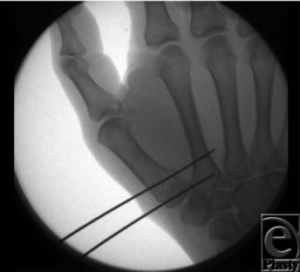

Nắn kín và xuyên đinh Kirchner: Di lệch đường gãy < 1mm. Đặt nẹp bột tư thế cố định 3 tuần